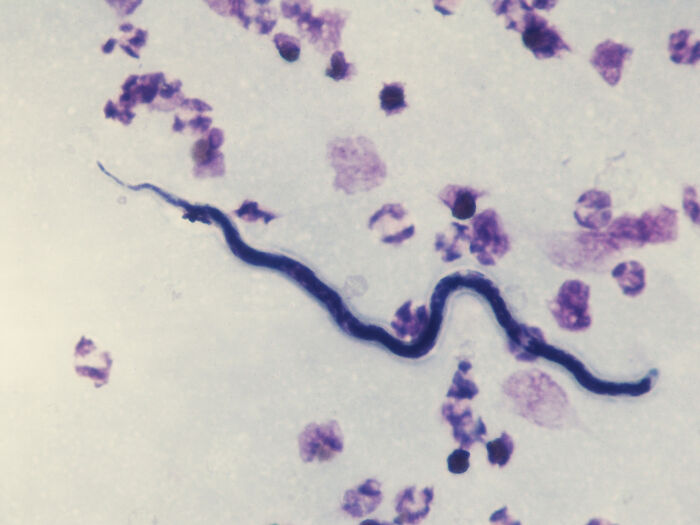

Ascaris worms are a type of large, parasitic roundworm that make their home in the human digestive tract. They are endemic in many parts of the world. I used to work at a hospital where we took a lot of patients from very poor and remote places, especially Central America, where roundworm infection is very common. When you put those patients under for surgery, the anesthesia causes their blood to become slightly alkaline, which the worms *hate*. So after a few minutes they will start coming out of *every orifice in the body*. Nose, mouth, r****m. And I'm talking full-sized worms that look just like earthworms. It is no cap one of the grossest things you can imagine.You give those patients a d**g called Bendazole, they poop dead worms for three days, and then they're fine.

Loa loa, the African Eye Worm, can invade the human eye. Adults are between 1 and 2.5 inches long.

More than 1.5 billion of people are currently infested with worms.